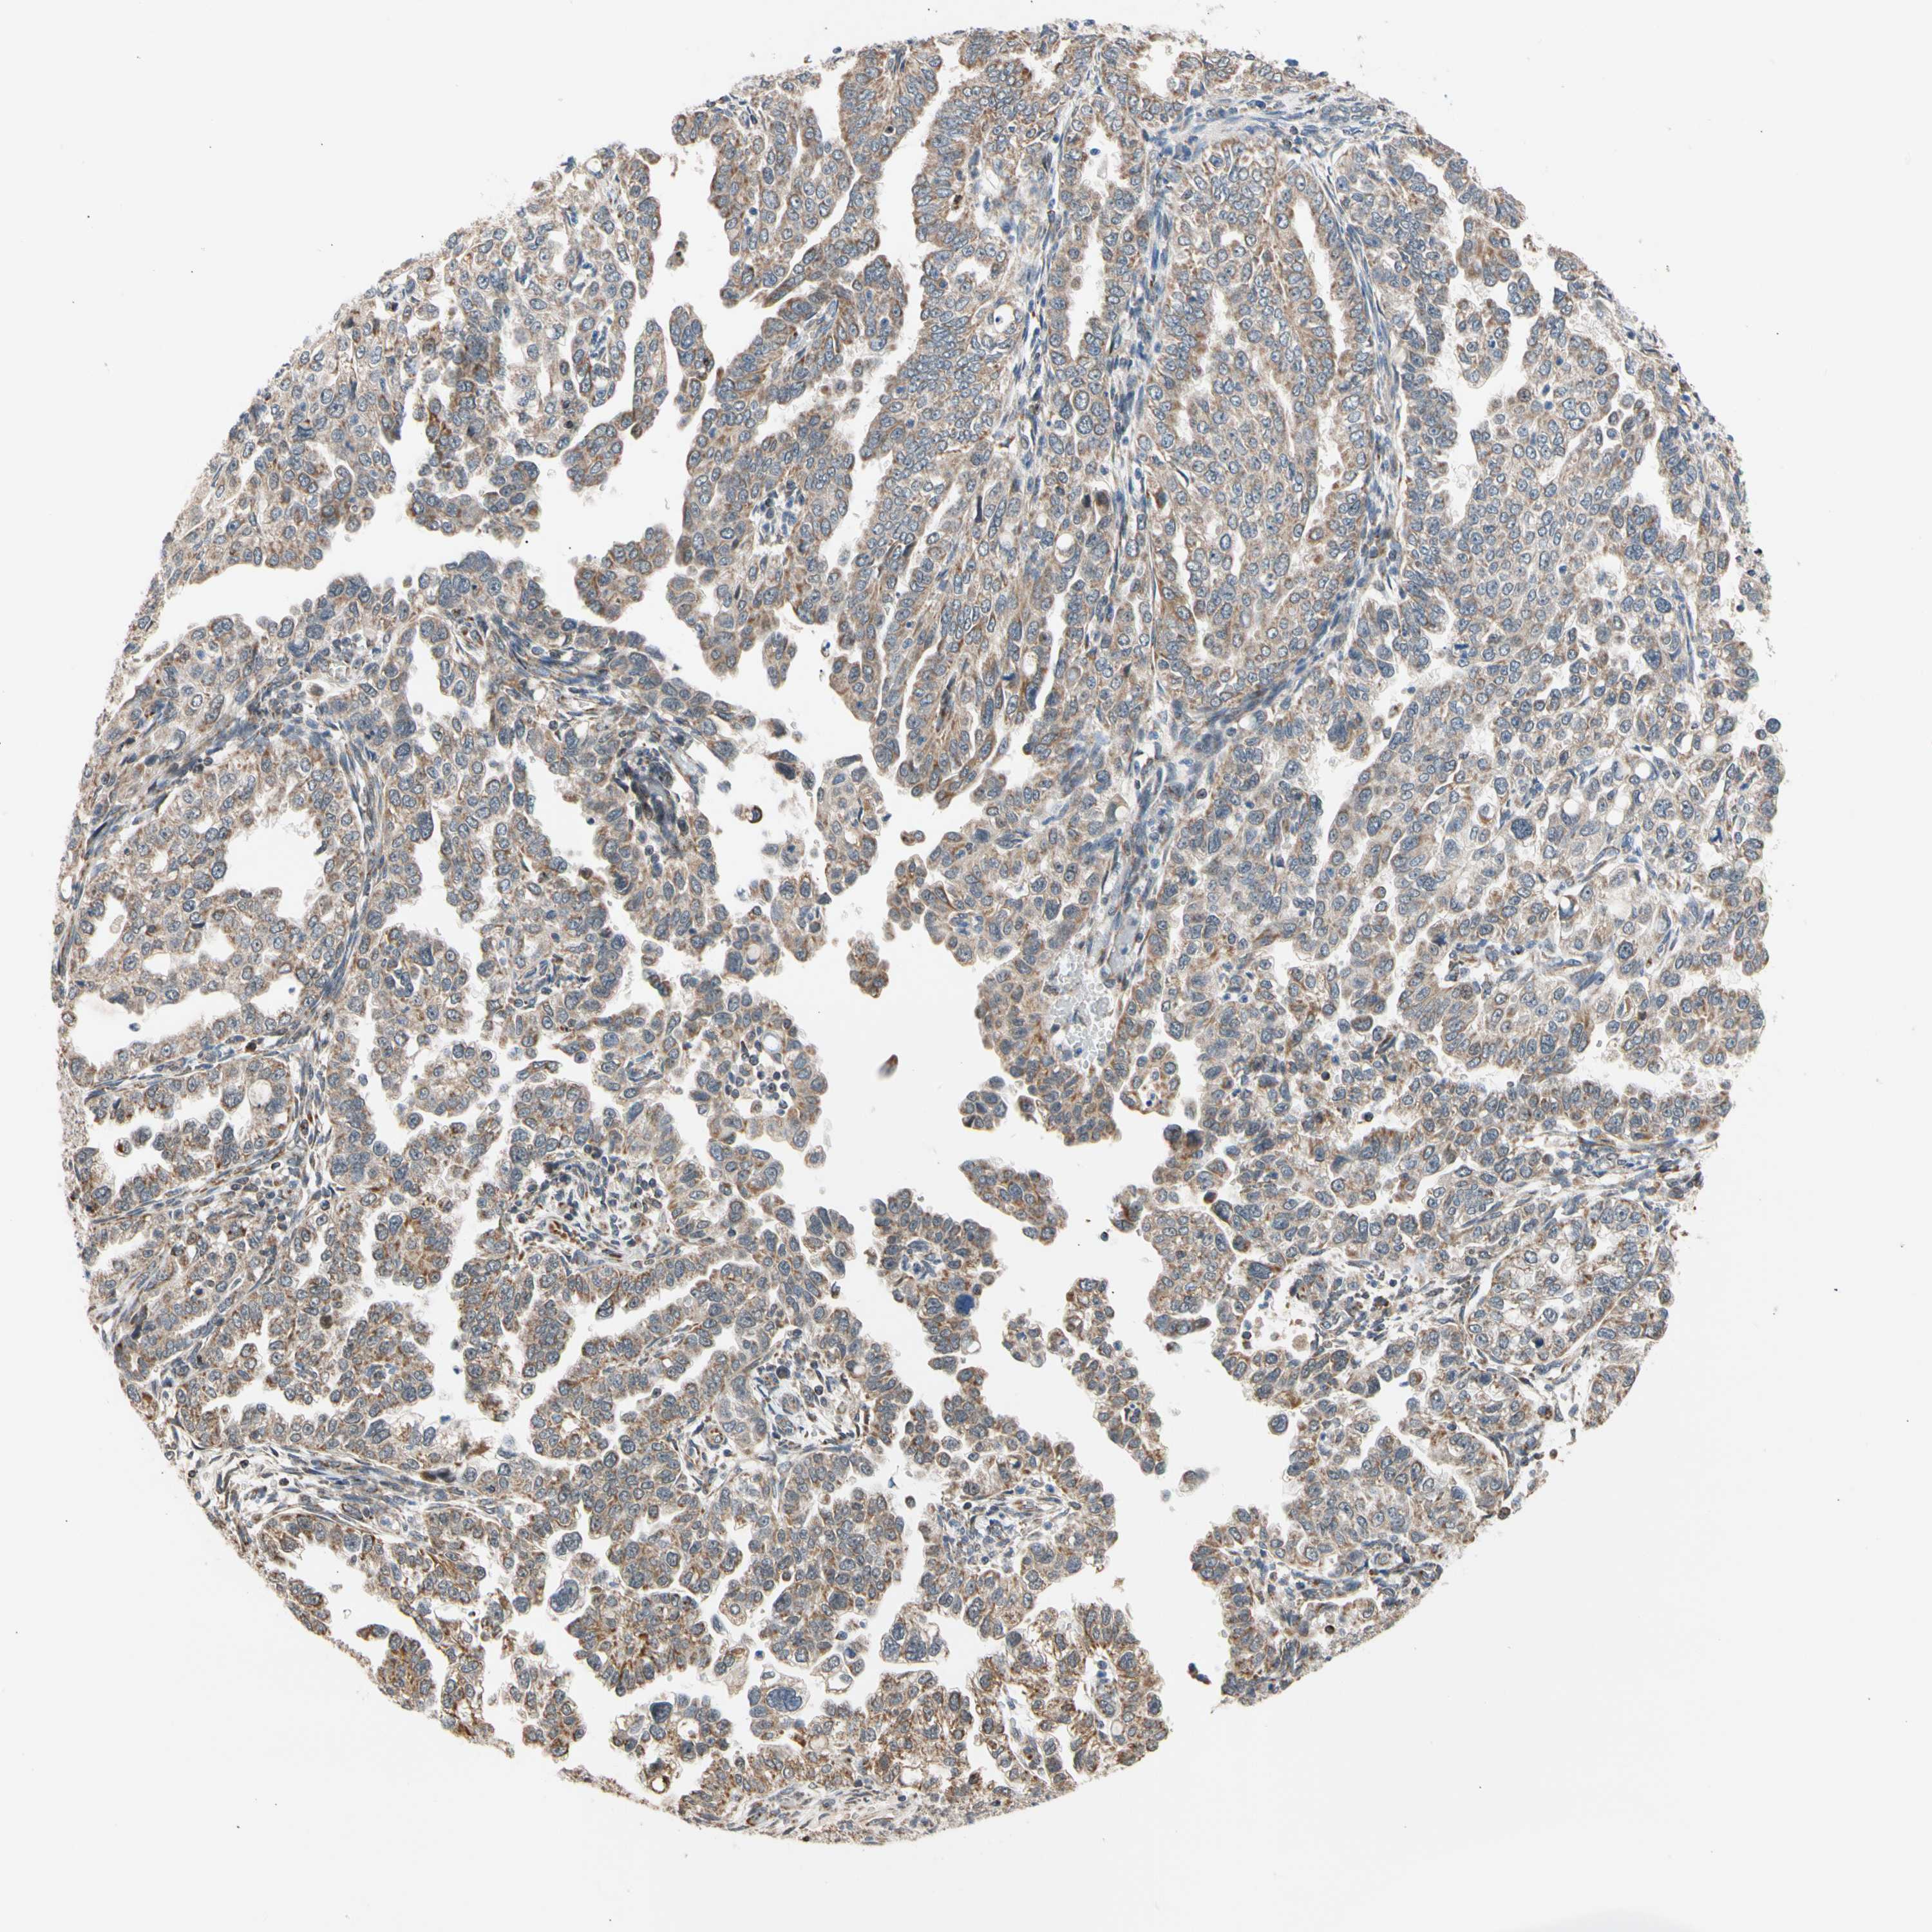

ENDOMETRIAL CANCER - Protein expressioni

A mouse-over function shows sample information and annotation data. Click on an image to view it in a full screen mode. Samples can be filtered based on level of antibody staining by selecting one or several of the following categories: high, medium, low and not detected. The assay and annotation is described here.

Note that samples used for immunohistochemistry by the Human Protein Atlas do not correspond to samples in the TCGA dataset.

Antibody stainingi

Antibody staining in the annotated cell types in the current human tissue is reported as not detected, low, medium, or high, based on conventional immunohistochemistry profiling in selected tissues. This score is based on the combination of the staining intensity and fraction of stained cells.

Each image is clickable and will lead to virtual microscopy that enables deeper exploration of all samples and also displays staining intensity scores, fraction scores and subcellular localization as well as patient and tissue information for each sample.

Antibody HPA008796

Staining

High

Medium

Low

Not detected

Intensity

Strong

Moderate

Weak

Negative

Quantity

>75%

75%-25%

<25%

None

Location

Nuclear

Cytoplasmic/membranous

Cytoplasmic/membranous,nuclear

Adenocarcinoma, NOS